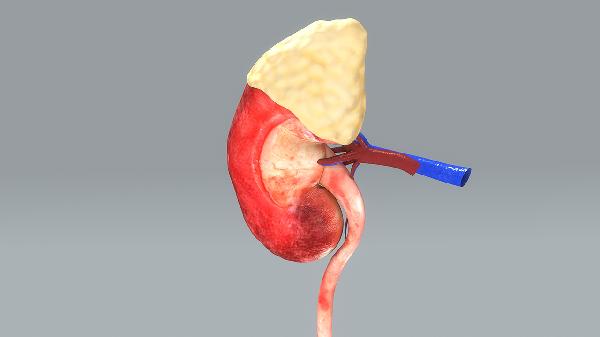

梅毒肾病的症状是什么

梅毒肾病是由梅毒螺旋体感染引起的肾脏损害,早期可能无明显症状,随着病情进展可出现蛋白尿、血尿、水肿、高血压及肾功能减退等表现。梅毒肾病症状主要有蛋白尿、血尿、水肿、高血压、肾功能异常。